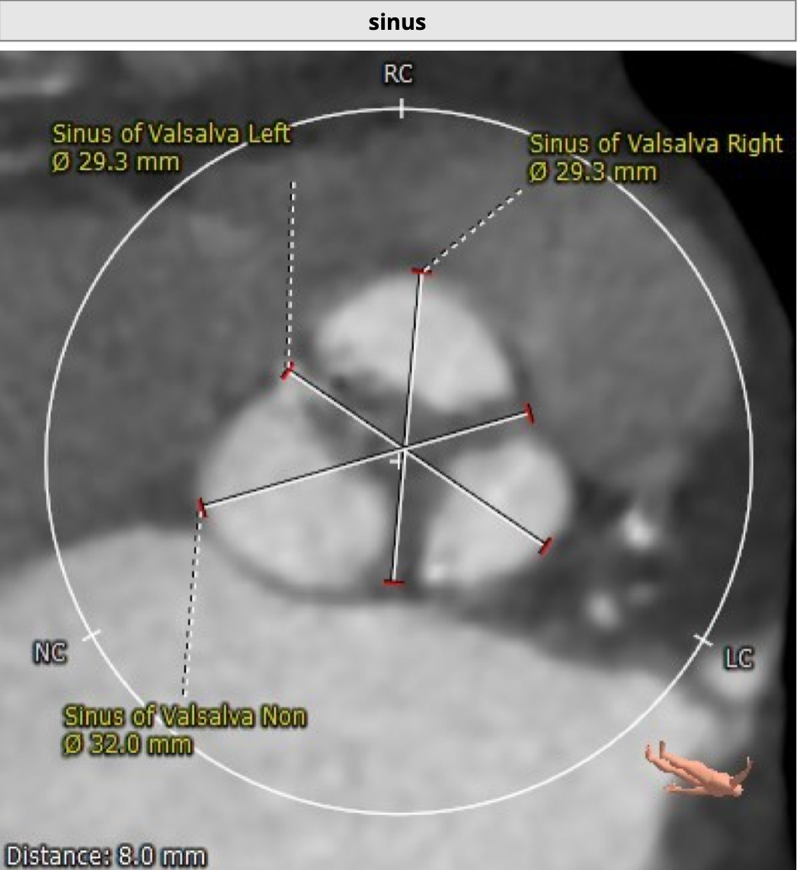

患者为73岁老年男性。CT评估显示其为三叶瓣,伴有轻度钙化,双冠高度可,升主动脉未见明显增宽,主动脉弓部角度平缓。瓣环最短径为17.6mm,最长径为24.7mm,平均瓣环直径为21.1mm。升主动脉平均直径33.6mm。左冠开口高度12.0mm,右冠开口高度14.2mm,冠脉阻塞风险低。外周血管未见明显钙化,最窄处直径为5.7mm。入路情况较佳。

主动脉窦